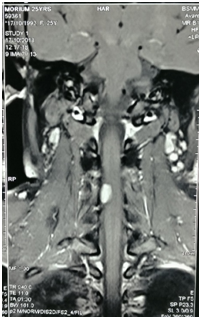

A 34years male admitted in our Department of Neurosurgery with the complaints of neck pain for 2year, progressive weakness of all limbs in the form of rotating paralysis starting with left upper limb followed by left lower limb, right lower limb & right upper limb for 15months without bowel bladder disturbance. On neurological examinations patients was found to be quadriparetic having muscle power MRC grade 3 on both side rendering her gait to be hemiplegic and walk with support. All her deep tendon reflexes were exaggerated. Hoffman sign was positive bilaterally.  Planters were bilaterally extensor. Ankle clonus was present bilaterally. He did not have any hypo or hyper pigmented patch in any part of the body. MRI of brain & cervical spine showed an intra-dural extra medullary lesion measuring about 5 x 3.5cm at foramen magnum extending both up and down situated posteriorly more on left side (Figures 4A-C). There was no other lesion on further cranial & spinal screening MRI.

Figure 4MRI of brain & cervical spine showed an intra-dural extra medullary lesion measuring about 5 x 3.5 cm at foramen magnum extending both up and down situated posteriorly more on left side.